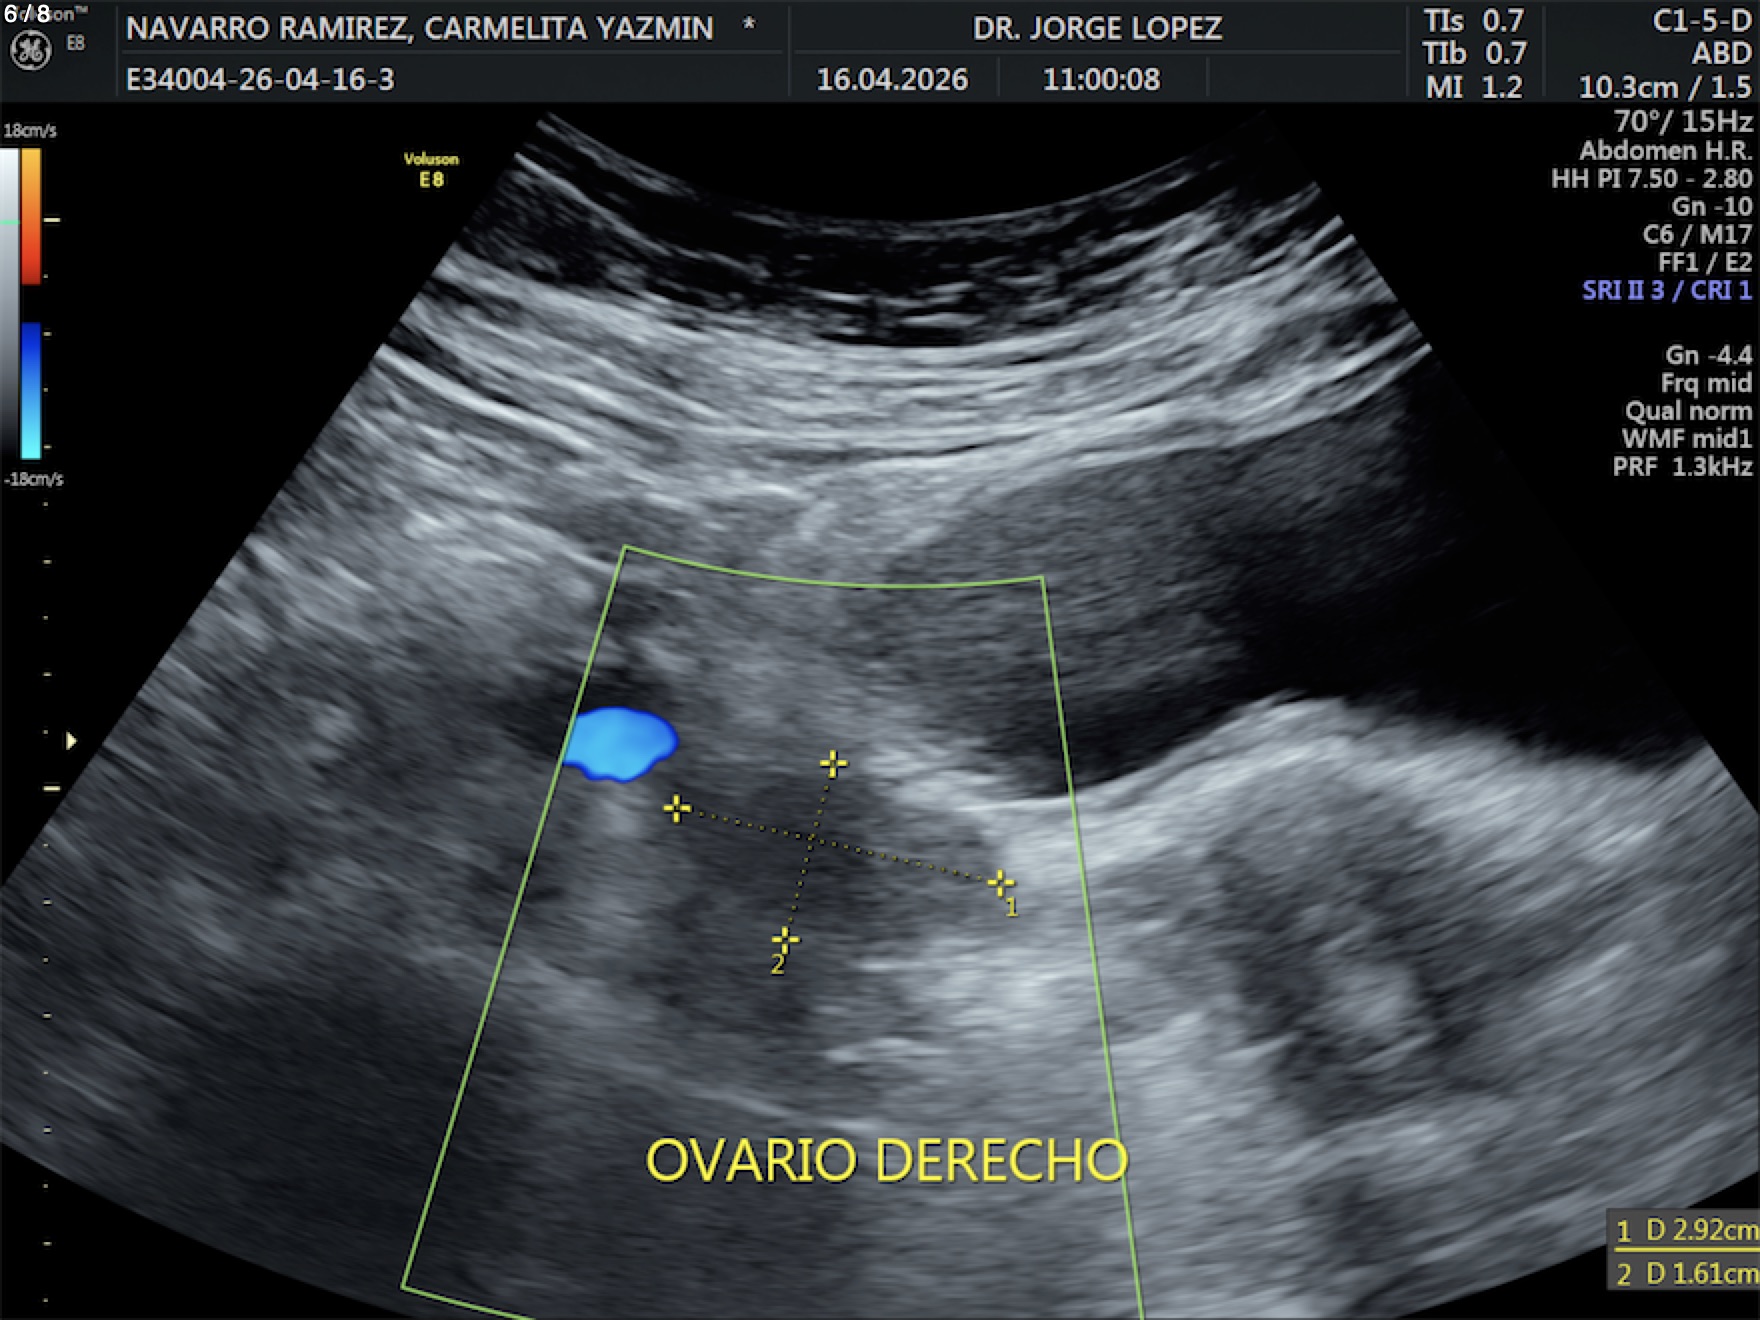

Navarro Ramirez Carmelita Yazmin - Unnamed